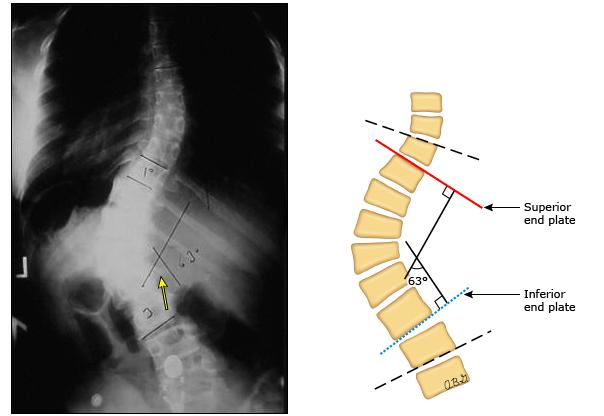

然而,究竟这个孩子能不能保守治疗,要不要做手术,从根本上,还是取决于侧弯本身的严重程度。而脊柱侧弯是否严重,取决于脊柱侧弯角度,也就是传说中的“Cobb角”(如下图)。这个角度越大,意味着侧弯越严重,越可能需要手术。